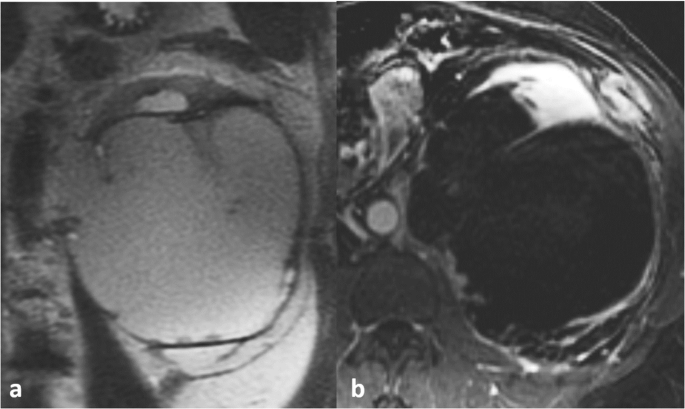

Regarding modality-specific features, all patients had heterogenous tumor enhancement on MRI and CT, and heterogenous T2 signal on MRI (Fig. 3). Of those patients who had diffusion-weighted imaging available for review (n = 11), all had diffusion restriction in the solid portions of the tumor. On MRI, T1 hyperintense hemorrhage was present in 7/12 (58 %) of cases (Fig. 4). No tumors had intravoxel fat on MRI. On CT, no tumors had calcifications. Of the three patients who had an FDG PET/CT, all had high metabolic activity (mean SUVmax 16.4, range 9.6–21.9), as shown in Fig. 5. An example of the gross and histologic features of one of the renal tumors is shown in Fig. 6.

38-year-old male with fumarate hydratase-deficient renal cell carcinoma (FH-RCC). On magnetic resonance imaging, axial post-contrast 3D fat-saturated T1-weighted sequence showing a left renal mass with heterogenous enhancement (a). 63-year-old male with FH-RCC, axial fat-suppressed T2-weighted sequence showing a right renal mass with heterogenous T2 signal (b)